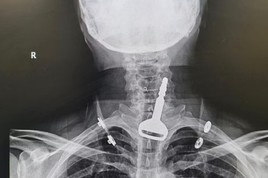

کنگ عبدالعزیز سپیشلسٹ ہسپتال  طائف نے میڈیکل ٹیم طلب کی۔ ڈاکٹر مھند فایز الذیب اور ڈاکٹر لطفی عبدالصمد نے میڈیکل ٹیم کی قیادت کی۔ ڈاکٹر آلا الھذلی نے دھاتی نٹ نکالنے کے لیے بچے کو اینستھیسیا دیا جس کے بعد اسے آپریشن روم لے جایا گیا جہاں سپیشل آلے کی مدد سے اس کے حلق سے دھاتی نٹ نکال لیا گیا۔

محکمہ صحت کا کہنا ہے کہ اب بچے کی حالت بہتر ہے اور اسے ہسپتال سے فارغ کردیا گیا ہے۔